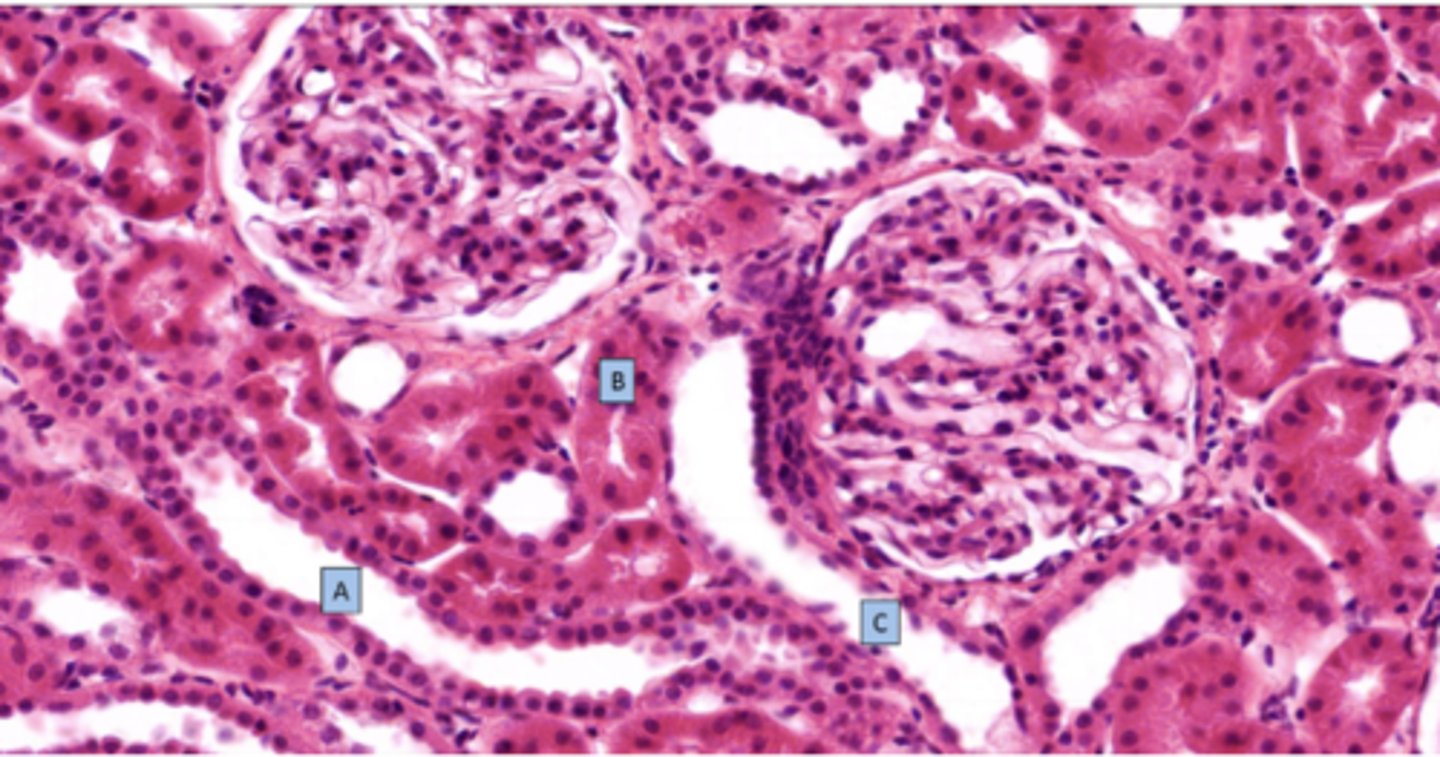

The arrow shows where filtrate enters what segment of the nephron

proximal convoluted tubule

What is the structure at C

distal convoluted tubule

Identify the structure of the nephron

glomerulus

Identify the structure of the glomerulus at 2

urinary pole